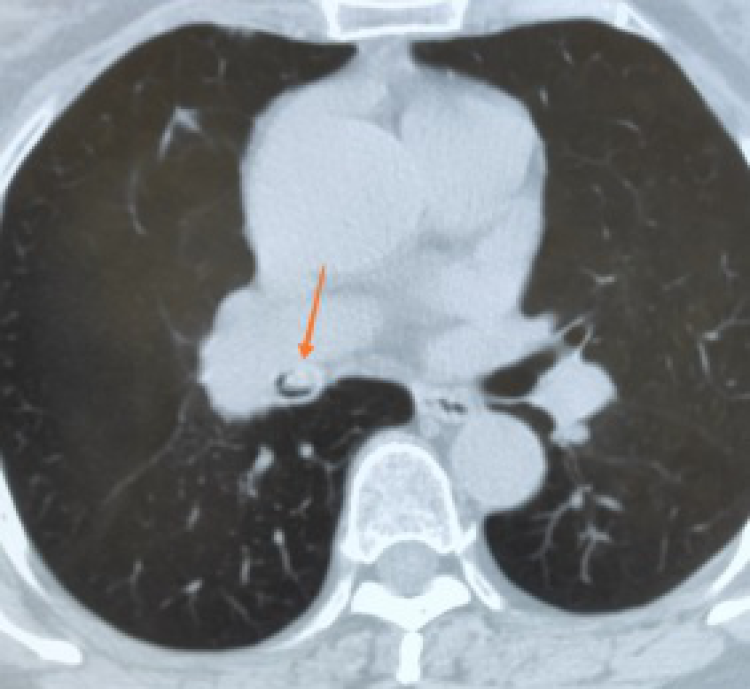

呼吸内科副主任医师杨华接诊后,详细询问了病史,了解到张女士三天前被食物河虾呛了一下,接着出现咳嗽,后出现咯血,就诊时张女士仍不停咯血且血量多,同时伴有胸痛,这一系列的症状引起了杨华的警觉,即刻安排张女士急诊CT,检查后发现患者右肺支气管有异物影,考虑为河虾呛入气管导致咳嗽咯血,情况危急,须紧急进行支气管镜。